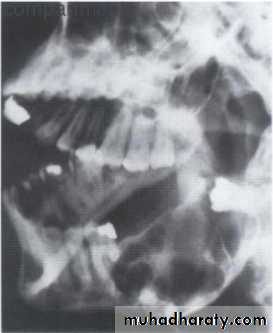

• 2.Position in the jaws:

• - Epicenter coronal to tooth- odontogenic epithelium.

• - Epicenter of the lesion is above the mandibular canal-odontogenic in origin .

• - Epicenter -below lDC- non odontogenic

Cystic ameloblastoma displaced IDC (odontogenic origin)

Epicenter coronal to tooth(odontogenic epithelium )